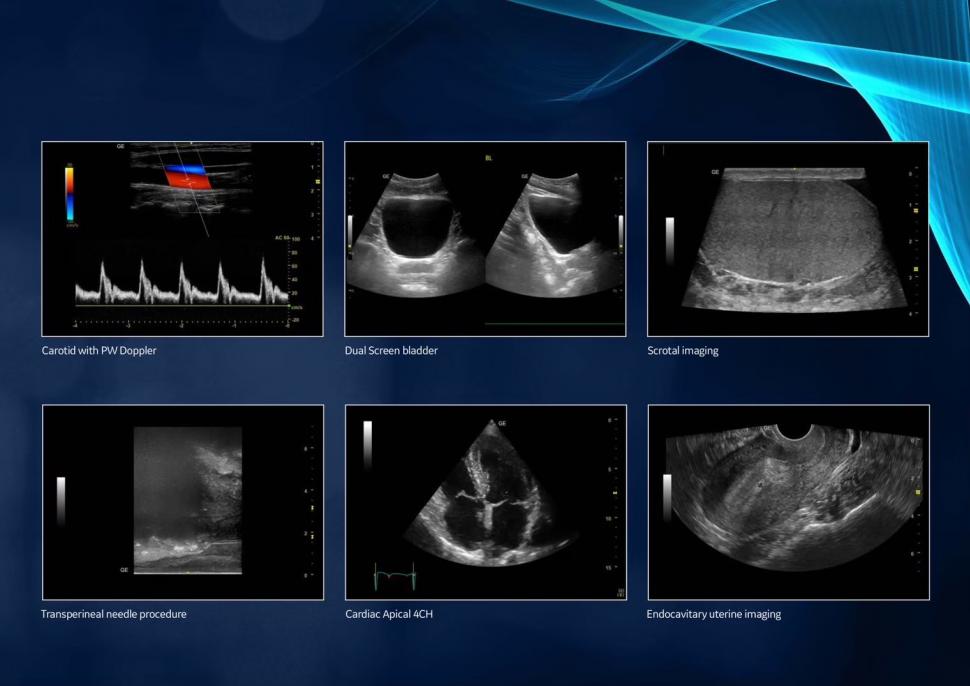

ชื่อเครื่อง

Versana Premier™ R2 เป็นเครื่องอัลตราซาวด์ (Ultrasound System) รุ่นพรีเมียมจากตระกูล Versana

คุณสมบัติเด่น

• พลังและความหลากหลาย: ใช้งานได้ครอบคลุมทั้งศูนย์วินิจฉัยโรค (imaging center), คลินิกทั่วไป, คลินิกเฉพาะทาง, คลินิกครอบครัว และโรงพยาบาล

• คุณภาพสูงและแม่นยำ: ผลิตภาพคุณภาพสูงอย่างสม่ำเสมอ ทั้งวันต่อวัน ผู้ป่วยต่อผู้ป่วย เพื่อช่วยให้วินิจฉัยได้อย่างแม่นยำ

• รองรับการตรวจที่หลากหลาย:

• Abdominal (ช่องท้อง)

• OB/GYN (สูติ-นรีเวช)

• Cardiac (หัวใจ)

• Small Parts (อวัยวะขนาดเล็ก เช่น ต่อมไทรอยด์)

• Urology (ทางเดินปัสสาวะ)

• Vascular (หลอดเลือด)

• Musculoskeletal (กล้ามเนื้อและกระดูก)

• Pediatric (กุมารเวช)

จุดเด่นเพิ่มเติม

• ถูกออกแบบมาเพื่อ ความอุ่นใจ (peace of mind) ของแพทย์และผู้ป่วย

• สามารถทำรายงานได้อย่าง ทันท่วงทีและแม่นยำ ส่งต่อให้แพทย์เจ้าของไข้และแพทย์ที่ส่งตรวจ